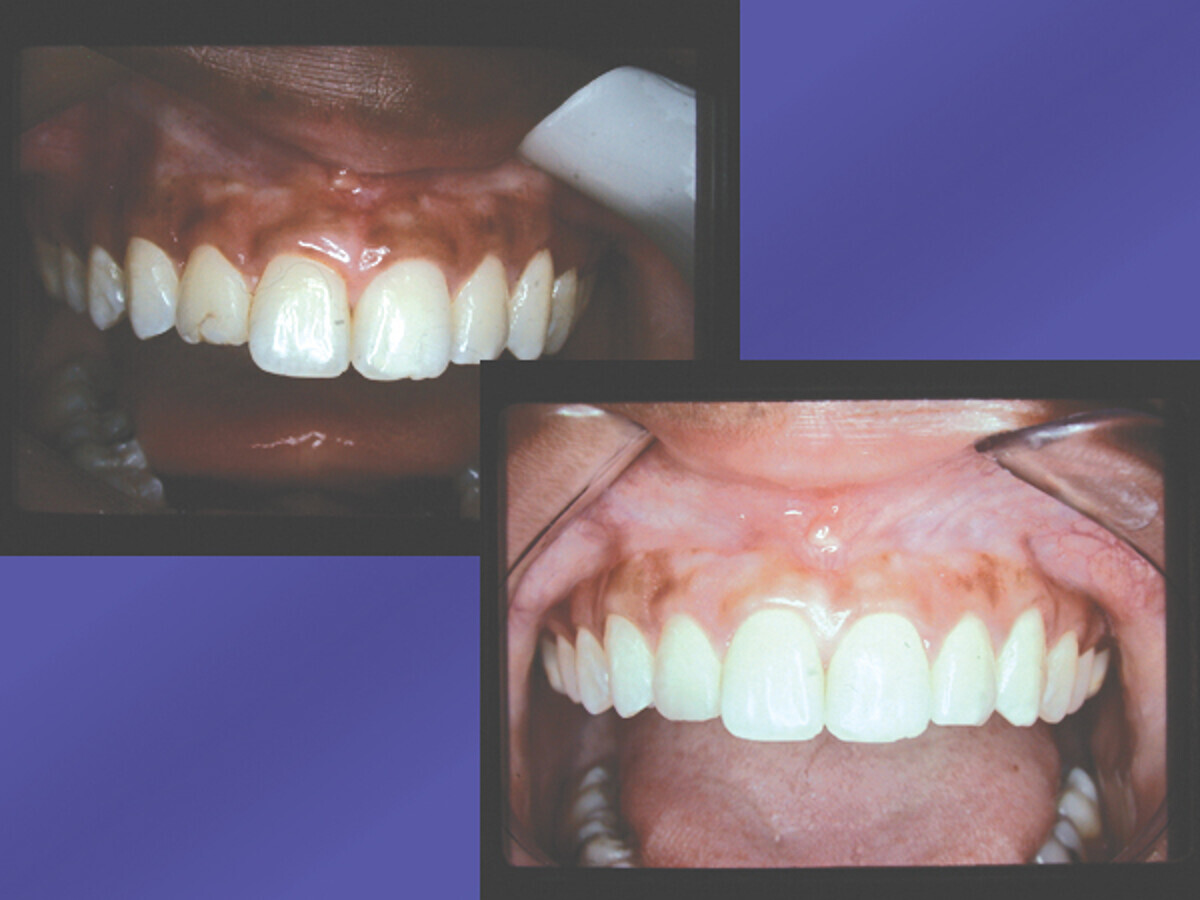

Fig. 2: Periodontal tissue repositioned sutured with sling suture technique. (Photo: Dr. David L. Hoexter)

Fig. 3: Healed periodontia. Enamel exposure full and natural. Tooth #7 restored. (Photo: Dr. David L. Hoexter)

The tissue was now placed at the desired level, usually at the symmetrical cervical height. Using the cuspid cervical height, in this case, the laterals and the centrals were positioned and sutured with a sling suture technique (Fig. 2) at the desired symmetrical level. Notice that the natural length of the incisors are exposed, but not the roots. The interproximal tissue is maintained to avoid the previously mentioned black-diamond appearing spaces that result when the interproximal tissues are removed. Notice the now exposed full enamel covering of the teeth involved, giving the length of the teeth the exposure required for the goal of “that smile” (Fig. 3). After the final stage, the young woman was ecstatic about her new bright smile. Her #7 was restored with a composite restoration. She maintains her oral health enthusiastically with oral hygiene, keeping the now healthy anterior periodontia maintained. The homogeneous color of the gingiva is symmetrical in lateral and vertical dimensions. There are no dark spaces interproximal, and the cervical symmetry of the teeth aid her ability to enjoy her glowing smile. The previously square-appearing teeth, are now restored to a natural, longer-appearing crown length, with the cervical gingiva on an even, lateral-linear appearance.